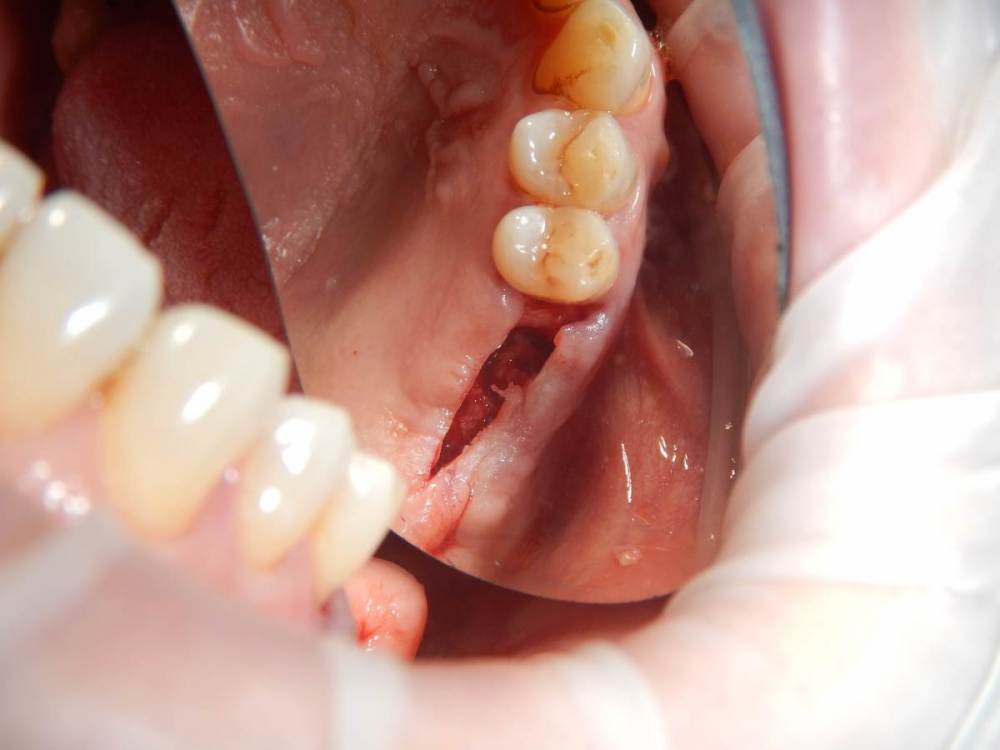

annda Опубликовано 11 июня, 2021 Поделиться Опубликовано 11 июня, 2021 (изменено) Ничего не беспокоит.Зубы удалены лет 15 назад Изменено 11 июня, 2021 пользователем annda 1 Ссылка на комментарий

Карен Аванесов Опубликовано 11 июня, 2021 Поделиться Опубликовано 11 июня, 2021 Анна здравствуйте. Версий много, вскрытие покажет, главное нет признаков воспаление, в любом случае интересный клинический случай под минимальное вмешательство, обязательно покажите развязку. 1 Ссылка на комментарий

Astronaft Опубликовано 11 июня, 2021 Поделиться Опубликовано 11 июня, 2021 Радиография была один в один с вашим случаем. Результат биопсии: рецидуальная киста с кристаллами холестерина. Но конечно может быть что-нибудь другое. 4 Ссылка на комментарий

annda Опубликовано 12 июня, 2021 Автор Поделиться Опубликовано 12 июня, 2021 (изменено) Спасибо всем. Вмешательства не было, кроме удаления. Я так понимаю, тактика заключается в доступе и банально кюретаже? Графт по убеждениям, дефект все одно получается практически четырехстеночный... Главное, не наджабить кортикалку ГП. Я так понимаю, процесс все же из пазухи, был с зубами связан? Изменено 12 июня, 2021 пользователем annda Ссылка на комментарий

Astronaft Опубликовано 12 июня, 2021 Поделиться Опубликовано 12 июня, 2021 (изменено) В моем случае процесс одонтогенный. Киста это остаток после удаления зуба. В вашем случае не должен быть из пазухи. Да - там есть истончение кортикальной пластины в одном месте, но вроде как без инвагинации. Границы везде четкие, т.е. процесс доброкачественный. Из пазухи в кость можно проникнуть только инвазивно. Лизис, а не раздвигание. Карцинома - границы были бы другие. Т.е. процесс либо происходит из самой кости, или одонтогенный. Изменено 12 июня, 2021 пользователем Astronaft 1 Ссылка на комментарий